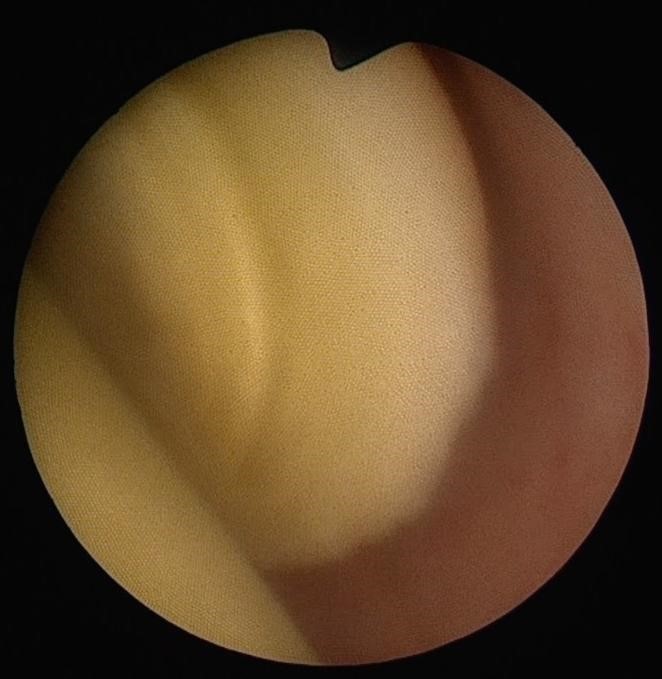

タンパク栓とは、PSP(Lactoferrin, Pancreatic stone protein:膵液タンパク質。最近ではLithostathine:リソスタチンとも呼ばれる)という物質からなる結石です。

膵液が逆流しうっ滞すると、膵液中のタンパク質が結晶として出現します。膵管内のタンパク成分が濃くなると、ここに塊ができます。これがタンパク栓です。

先天性胆道拡張症の症状である腹痛や肝機能異常、高アミラーゼ血症は、タンパク栓が胆管や膵管に詰まり、胆汁や膵液がたまって胆管・膵管の内圧が上昇することで起こります。膵・胆管合流異常があった場合でも、このタンパク栓が悪さをしない限り、ほとんど症状が現れません。